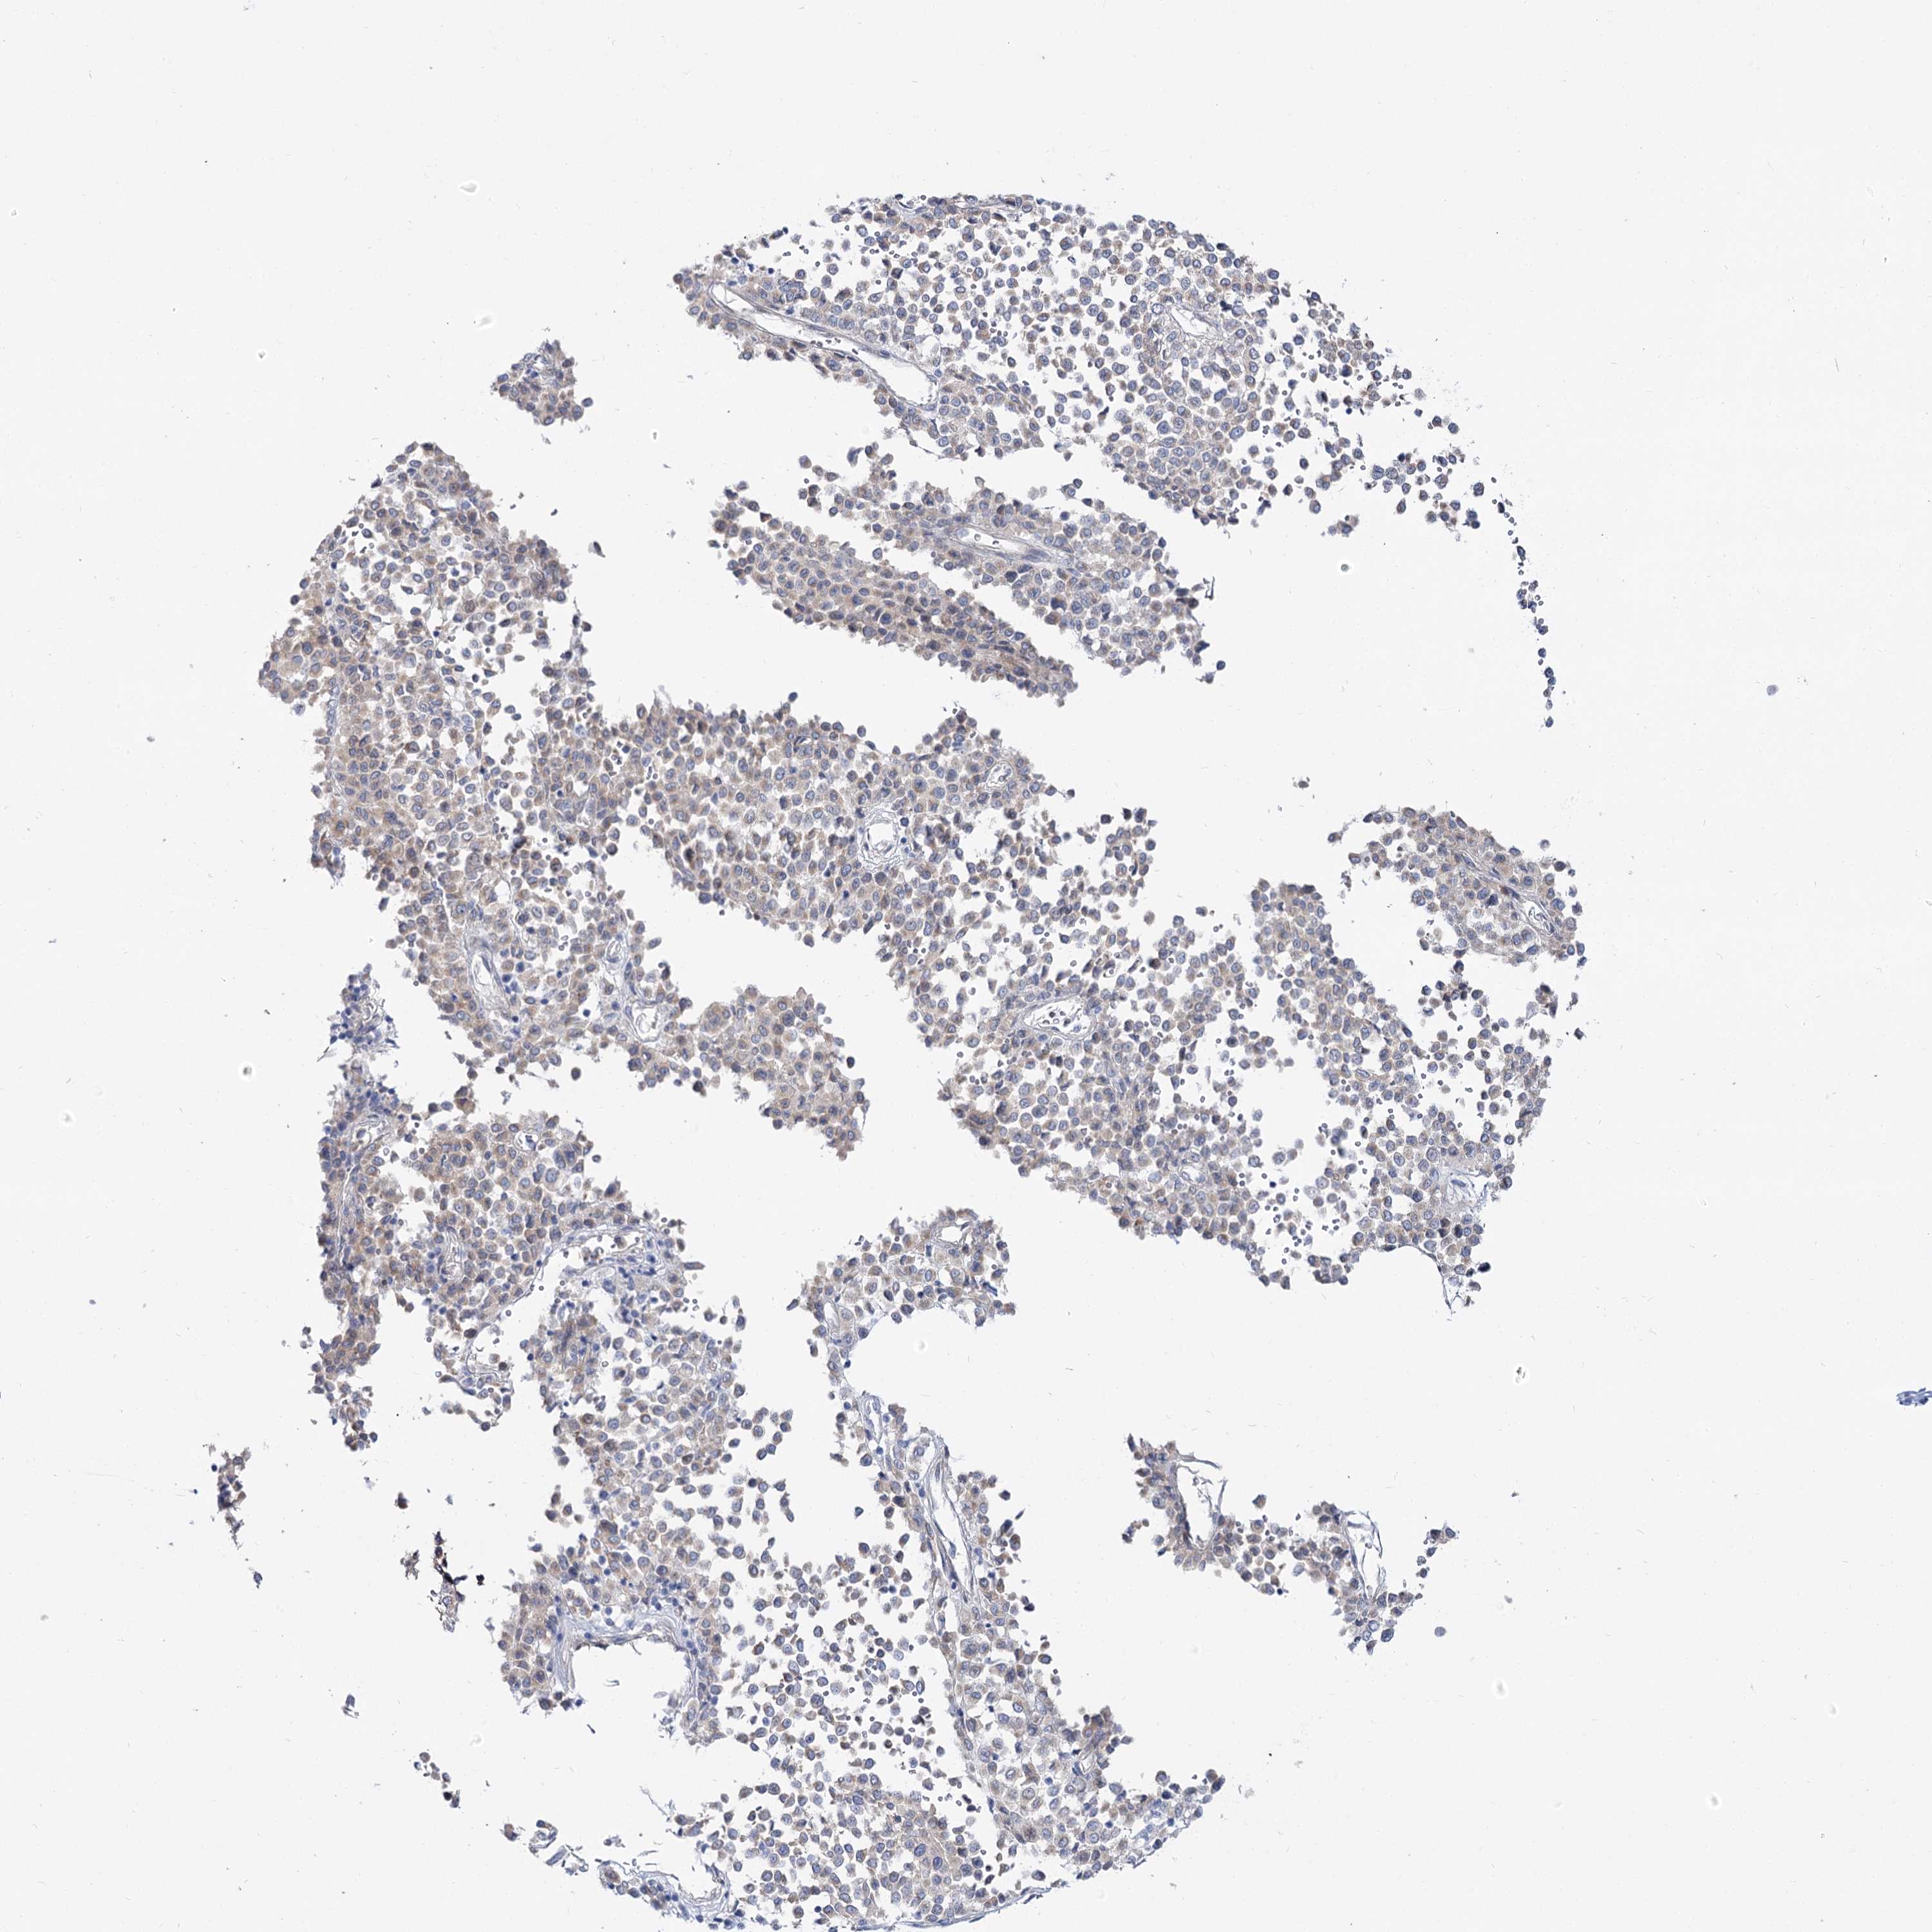

MELANOMA - Protein expressioni

A mouse-over function shows sample information and annotation data. Click on an image to view it in a full screen mode. Samples can be filtered based on level of antibody staining by selecting one or several of the following categories: high, medium, low and not detected. The assay and annotation is described here.

Note that samples used for immunohistochemistry by the Human Protein Atlas do not correspond to samples in the TCGA dataset.

Antibody stainingi

Antibody staining in the annotated cell types in the current human tissue is reported as not detected, low, medium, or high, based on conventional immunohistochemistry profiling in selected tissues. This score is based on the combination of the staining intensity and fraction of stained cells.

Each image is clickable and will lead to virtual microscopy that enables deeper exploration of all samples and also displays staining intensity scores, fraction scores and subcellular localization as well as patient and tissue information for each sample.

Antibody HPA038208

Antibody HPA038209

Staining

High

Medium

Low

Not detected

Intensity

Strong

Moderate

Weak

Negative

Quantity

>75%

75%-25%

<25%

None

Location

Nuclear

Cytoplasmic/membranous

Cytoplasmic/membranous,nuclear

Malignant melanoma, NOS

Malignant melanoma, Metastatic site